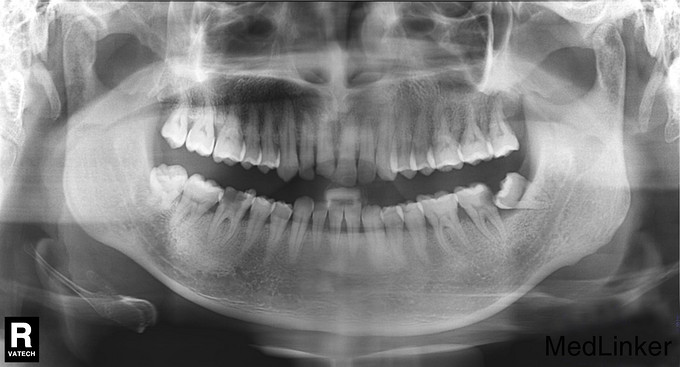

检查:颌面部左右基本对称,开口度及开口型正常。38近中低位阻生,未探及龋坏,叩痛(—),无明显松动,牙龈无明显红肿;37合面及远中见龋损,龋洞内大量嵌塞食物,腐质较多,探痛明显,叩痛(—),无明显松动,牙龈无明显红肿。 X线示:38 近中低位阻生,双根,37 远中邻面低密度影像至髓,根尖区未见明显异常。

诊断:1、38近中阻生 2、37慢性牙髓炎 治疗计划:1、拔除38阻生齿 2、37根管治疗后冠修复 治疗:1. 37利多卡因局麻下,去腐未净露髓,暴露髓腔,降牙合,探及MB、ML、D三个根管口,置非砷慢失活剂,氧化锌水门汀暂封。嘱勿用患牙咬物。 38利多卡因局麻下分龈,去除近中阻力,挺松,拔除,搔刮牙槽窝,复位,局部压迫止血。 2.主诉:左下后牙上次治疗后无不适。 检查:37暂封物在,叩痛(—),牙体无松动,牙龈无明显红肿。 处置:37去除暂封物,拔残髓,10号C锉疏通根管,干燥根管,电测工作长度WL:MB=ML=18mm,D=18.5mm。EDTA下,常规预备至35#,3%过氧化氢和生理盐水冲洗+超声荡洗根管交替进行。隔湿,干燥根管,封CP棉球, 氧化锌水门汀暂封。嘱勿用患牙咬物。 3.主诉:左下后牙上次治疗后无不适。 检查:37暂封物在,叩痛(—),牙体无松动,牙龈无明显红肿。 处置:37去除暂封物,取出棉球,生理盐水冲洗并干燥根管,复测工作长度同前:MB=ML=18mm,D=18.5mm。进口根充糊剂+牙胶尖冷侧压根管充填,氧化锌水门汀暂封,术后拍片示:37根充恰填。嘱勿用患牙咬物。 建议:37桩冠修复

下颌第三磨牙是临床中最常见的阻生牙,在萌出的时候由于受到软组织、邻牙、骨组织的影响而造成阻生。由于阻生的位置特殊,紧邻重要的解剖结构,可引起冠周炎、间隙感染、龋齿、牙髓炎等并发症,特别是有部分病例,就诊时第二磨牙的牙根吸收已经无法保留,从而影响口腔的正常功能。 在本病例中,左侧下颌第三磨牙发生近中阻生,抵住下颌第二磨牙的远中面生长,早期下颌第三磨牙阻生过程中的冠周炎症状不明显,而和第二磨牙之间经常会出现食物嵌塞。由于位置隐蔽不易清洁,使得下颌第二磨牙的远中龋坏形成,甚至发生部分牙齿吸收的现象,引起患者疼痛不适,此时就诊时第二磨牙已出现了牙髓的病变。如若未及时就诊处置,病变发展到晚期,常可导致邻近第二磨牙的牙根吸收,使其松动,造成第二磨牙无法保留。因此,是否应预防性拔除阻生下颌第三磨牙呢? 拔牙适应症指出:常发生冠周炎、引起邻牙牙根吸收或破坏时应拔除,不过目前对于什么样的阻生下颌第三磨牙需要预防性拔除仍存在争议。下颌第三磨牙错位萌出,牙冠与龈瓣之间可形成较深的盲袋,引起冠周炎的发生,严重时会发生邻近的组织间隙感染,甚至引起口底蜂窝织炎。此外,错位萌出可造成合创伤,冠边缘的粘膜发生溃疡、糜烂等,引起颞下颌关节紊乱疾病及粘膜的病理性损害等。但是,下颌阻生第三磨牙距离下颌神经管近,牙根可在下颌管的上方、侧方甚至直接接触,特别是低位和埋伏阻生的,进行阻生牙拔除的时候易损伤下牙槽神经。因此,临床上需要根据患者的实际情况综合考虑再决定拔除与否。